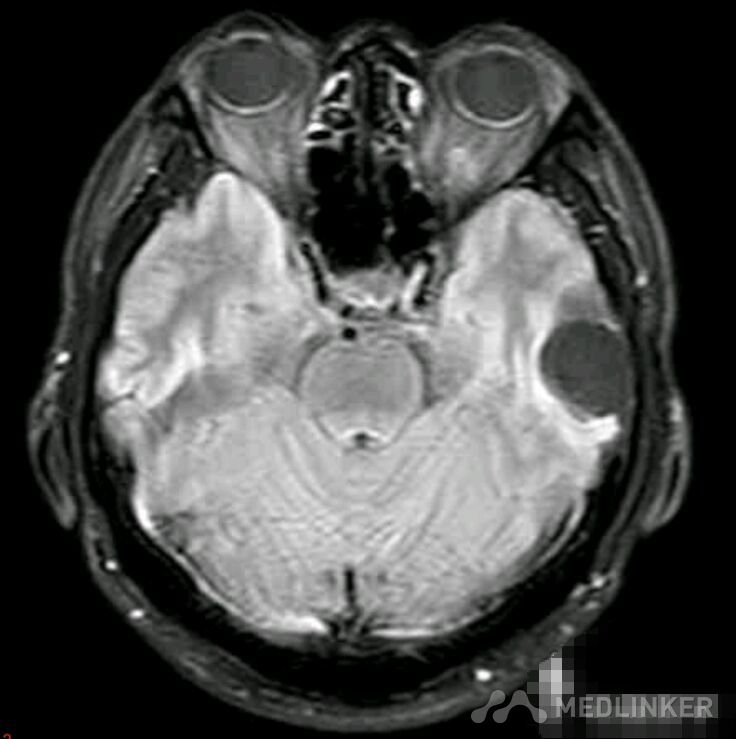

脑囊虫病高清影像资料分享

脑囊虫病经典资料